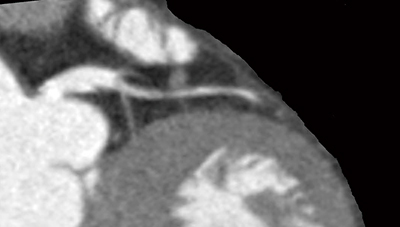

図3 陳旧性心筋梗塞と狭心症の合併例

過去に右冠動脈#3に急性心筋梗塞(ステント治療による再灌流療法に成功)を発症し,最近狭心痛が見られたので,心臓CT,負荷心筋SPECT,冠動脈造影検査を受けた。負荷心筋SPECTでは,広範下壁と前壁の一部に血流低下を認め,冠動脈造影所見と一致していることが判断される。心臓CTでは個々の冠動脈病変に対応する支配灌流域(心筋リスク領域)を算出することが可能であり,この症例では第二対角枝の治療意義について検討することが可能であった。